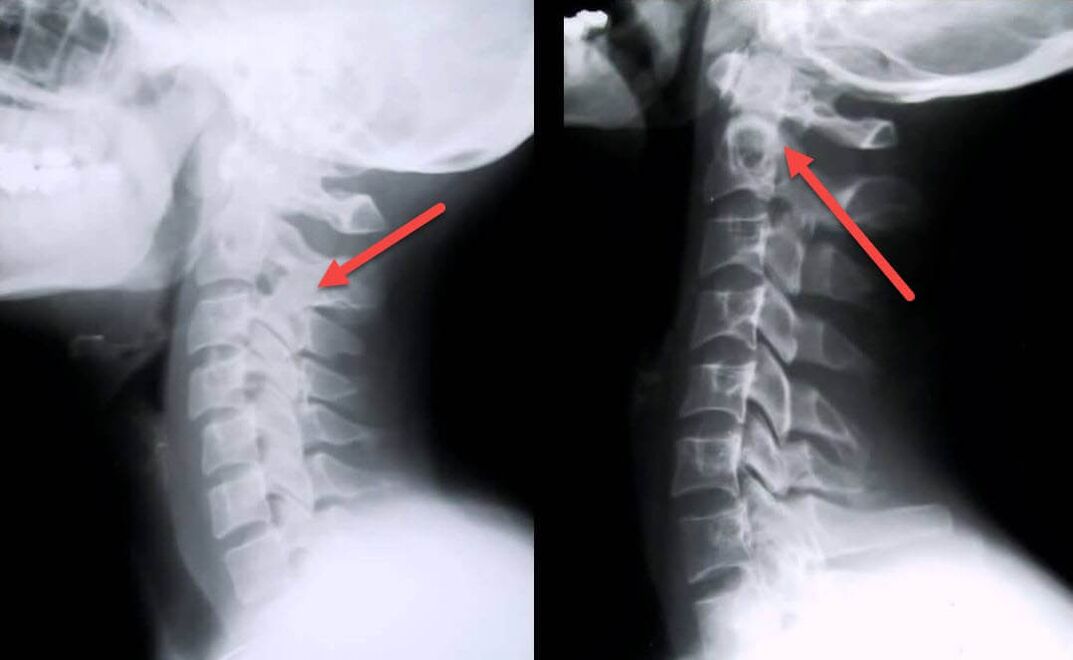

The most informative diagnostic procedure is x-ray.1st degree pathologies correspond to the 1st or 2nd radiological stage.The resulting images display typical signs of the disease.

| Radiographic stages of 1st degree cervical osteochondrosis | Characteristic signs |

|---|---|

| Phase 1 | Small changes in the curvature of the spine in the cervical region, affecting one or more segments |

| Phase 2 | Slight thickening of the intervertebral discs, deformation of the uncinate processes, straightening of the lordosis, slight growths of the bone structures |